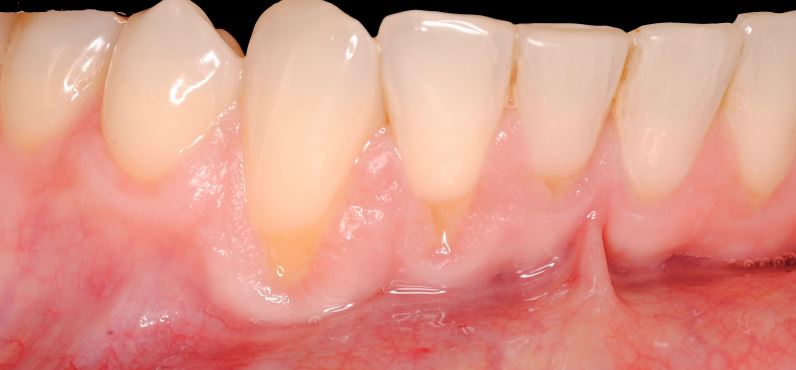

Objetivos periodontales: Mediante ingerto de tejido conectivo subepitelial de paladar con técnica de tunelización.

- Cobertura radicular en recesiones múltiples

- Estabilidad periodontal mejorando el biotipo gingival

- Mejora sensibilidad

Fotografías del proceso: